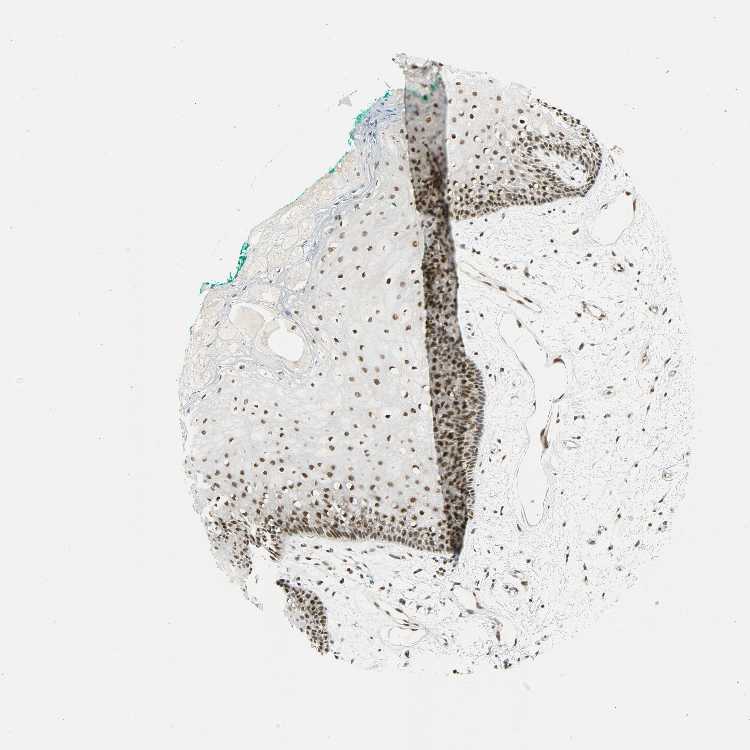

TISSUE PRIMARY DATA ORAL MUCOSA Show tissue menu

ORAL MUCOSA - Antibody stainingi

Antibody staining in the annotated cell types in the current human tissue is reported as not detected, low, medium, or high, based on conventional immunohistochemistry profiling in selected tissues. This score is based on the combination of the staining intensity and fraction of stained cells.

Each image is clickable and will lead to virtual microscopy that enables deeper exploration of all samples and also displays staining intensity scores, fraction scores and subcellular localization as well as patient and tissue information for each sample.

Antibody HPA004890

Squamous epithelial cells High